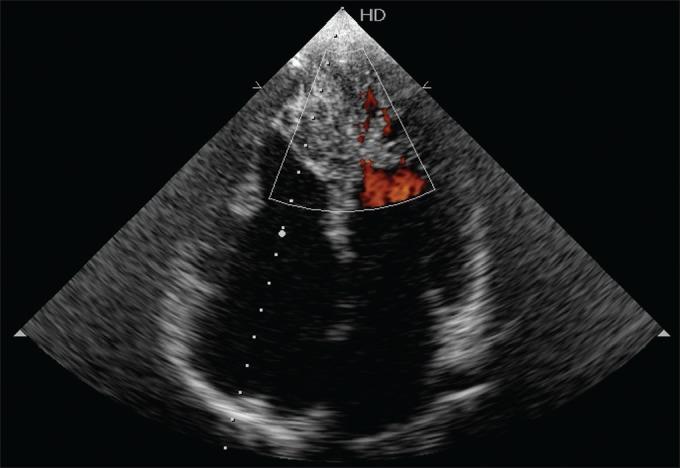

A 34 year-old male patient presented with recurrent attack of palpitation and chest pain due to Wolf Parkinson White syndrome (WPWS). Two dimensional echocardiography demonstrated features of Ebstein's anomaly along with biventricular non compaction. Color flow Doppler studies confirmed the presence of blood flow within the trabeculations. Biventricular myocardial non-compaction associated with Ebstein's anomaly who presented with WPWS is a very rare association. So far, Medline search revealed only three reported cases in the literatures. The patient was treated with radiofrequency ablation of right sided posteroseptal accessory pathway of WPWS and was asymptomatic in further follow-up.

一名34岁男性患者因预激综合征(WPWS)出现反复发作的心悸和胸痛。二维超声心动图显示埃布斯坦畸形特征以及双心室心肌致密化不全。彩色多普勒血流显像研究证实小梁内存在血流。伴有埃布斯坦畸形且出现WPWS的双心室心肌致密化不全是一种非常罕见的关联。到目前为止,医学文献在线数据库搜索显示文献中仅报道了3例。该患者接受了WPWS右侧后间隔旁路的射频消融治疗,后续随访中无症状。